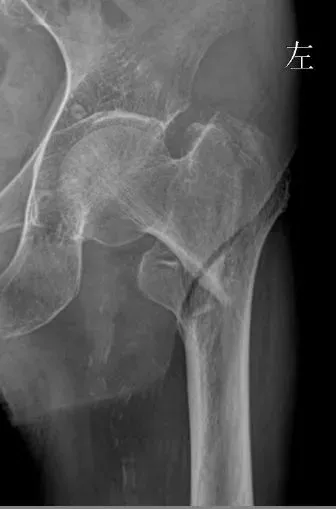

案例一

94歲的患者在家中疊被子時不慎摔倒,導(dǎo)致左下肢疼痛伴活動受限。家屬緊急將其送往渭北中心醫(yī)院。急診DR檢查顯示:左側(cè)股骨中段骨折,左側(cè)人工股骨頭置換術(shù)后改變。

術(shù)前

入院后,關(guān)節(jié)骨科(骨一科)團隊迅速對患者進行全面評估,經(jīng)過影像科、呼吸內(nèi)科、麻醉科、醫(yī)務(wù)科等多學(xué)科會診討論(MDT),考慮到患者高齡及復(fù)雜病情,決定實施左股骨干骨折切開復(fù)位內(nèi)固定術(shù)。